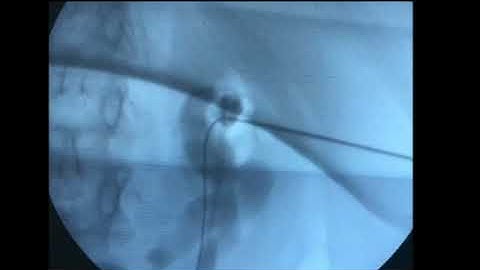

PCNL Access with Fluoroscopy Triangulation Technique